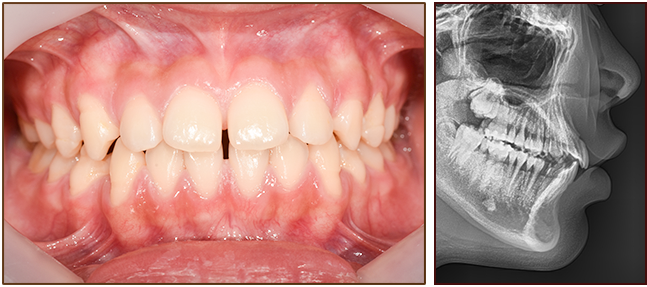

교정 전

교정 후